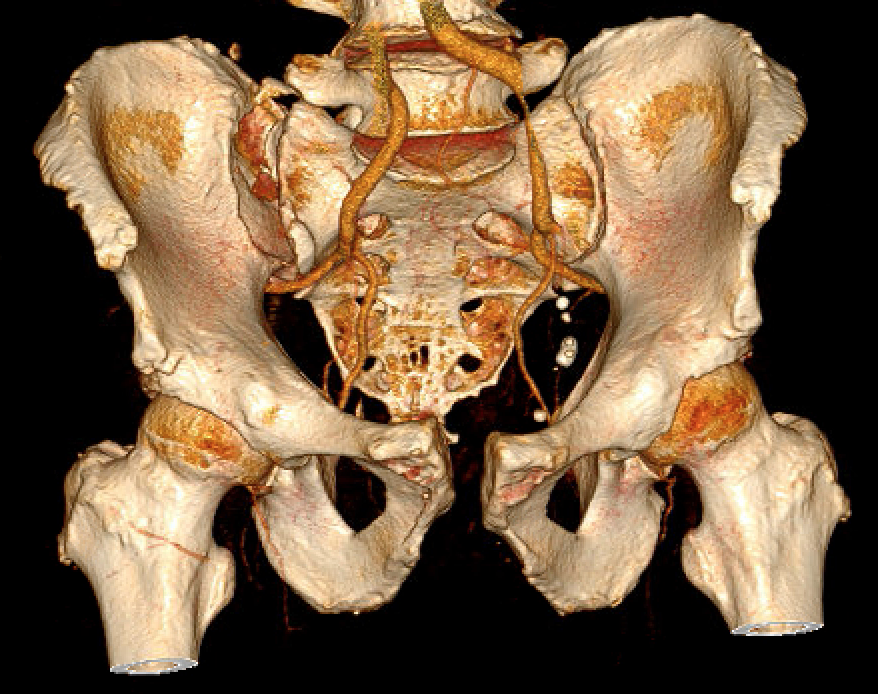

LC-1: pubic rami fracture with sacral fracture

LC-2: Pelvic wing fracture with pubic rami fracture

Crescent fracture variant

Iliac wing fracture that extends into sacrum and associated with SI joint dislocation

Crescent fracture